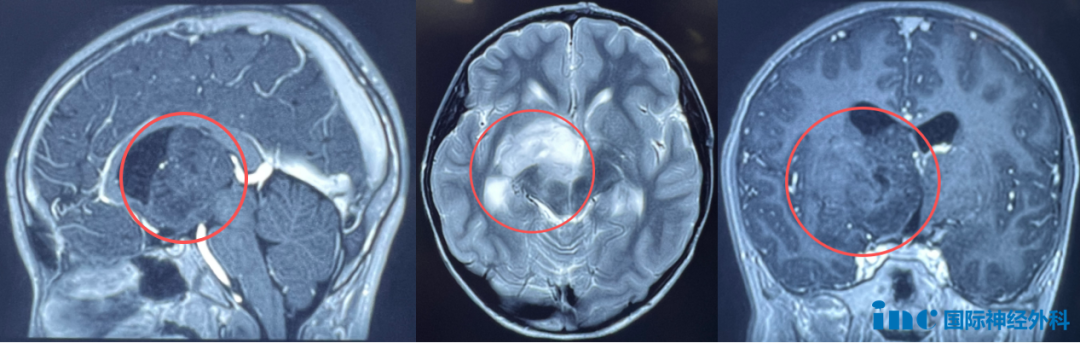

小航的健康问题始于一次意外检查,发现其右侧丘脑-基底节区存在一个巨大肿瘤。该区域属于大脑深部的重要结构,二者功能密切相关。丘脑作为感觉信息传递的中继站,基底节区则参与运动控制与认知功能,两者通过神经环路相互连接,共同调节运动、感觉及高级神经活动。手术过程中若有丝毫偏差,都可能损伤关键神经功能,给患者带来毁灭性后果,例如偏瘫、视野缺损、失语甚至昏迷等。

更为棘手的是,影像学检查显示肿瘤已呈现弥漫性生长趋势,脑室扩大,脑脊液循环开始受到影响。父母不敢有丝毫耽搁,迫切希望为孩子解决病痛。

(达恩的术前MRI影像)

(小正的术前MRI影像)